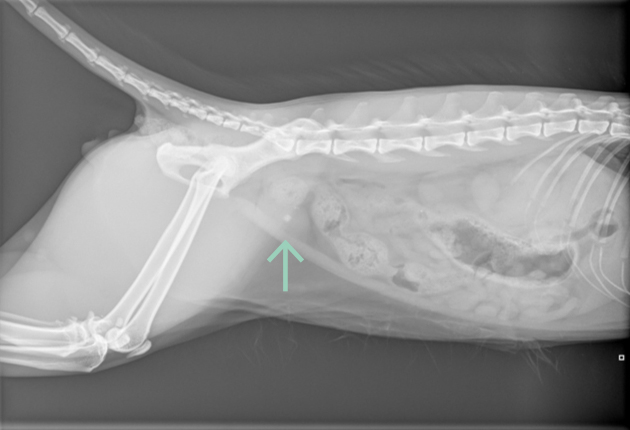

De dierenarts kan met microscopisch onderzoek van de urine vaststellen of er sprake is van blaasgruis. Afhankelijk van het type blaasgruis kan dit vaak worden opgelost met een speciaal dieet. Met een echo of röntgenfoto kan worden vastgesteld of er een blaassteen aanwezig is; deze moet meestal operatief worden verwijderd. In het zeldzame geval van een bacteriële infectie wordt een antibioticumkuur voorgeschreven.